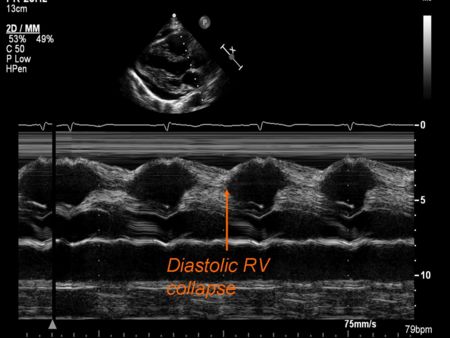

- Tamponade - diastolic collapse

M Mode in Tamponade

- Diastolic collapse of the right ventricle